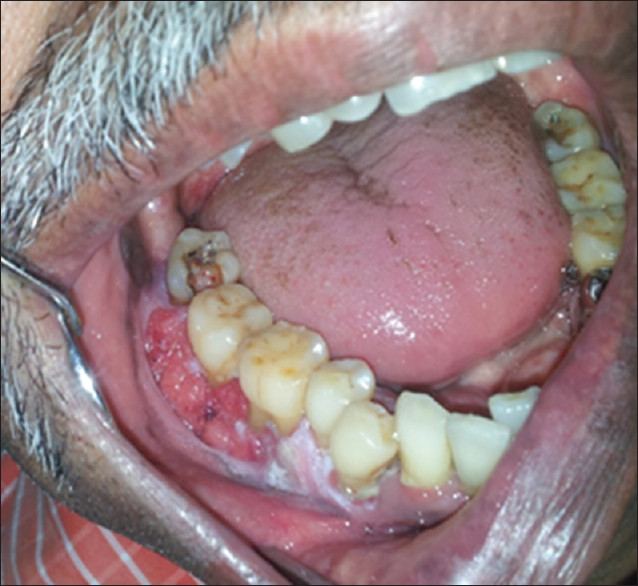

Periodontal Disease

The evidence is overwhelming that smoking contributes to periodontal disease (see Right) and that continued smoking results in a reduced response to periodontal treatment. There is a greater amount of bone loss around teeth in smokers and individuals who smoke are more likely to lose teeth than nonsmokers. It is reported that more than half of advanced gum disease can be linked to tobacco use.

Gingival Recession and Tooth AbrasionIn addition to the development of changes to the oral tissues, the use of smokeless tobacco can damage both the gum tissue and the teeth in the area where it is held in the mouth. Smokeless tobacco can result in localized gum recession and the exposed teeth often develop dental decay due the sweetener in smokeless tobacco. Unfortunately, stopping the tobacco use does not reverse the gum problem or tooth decay.